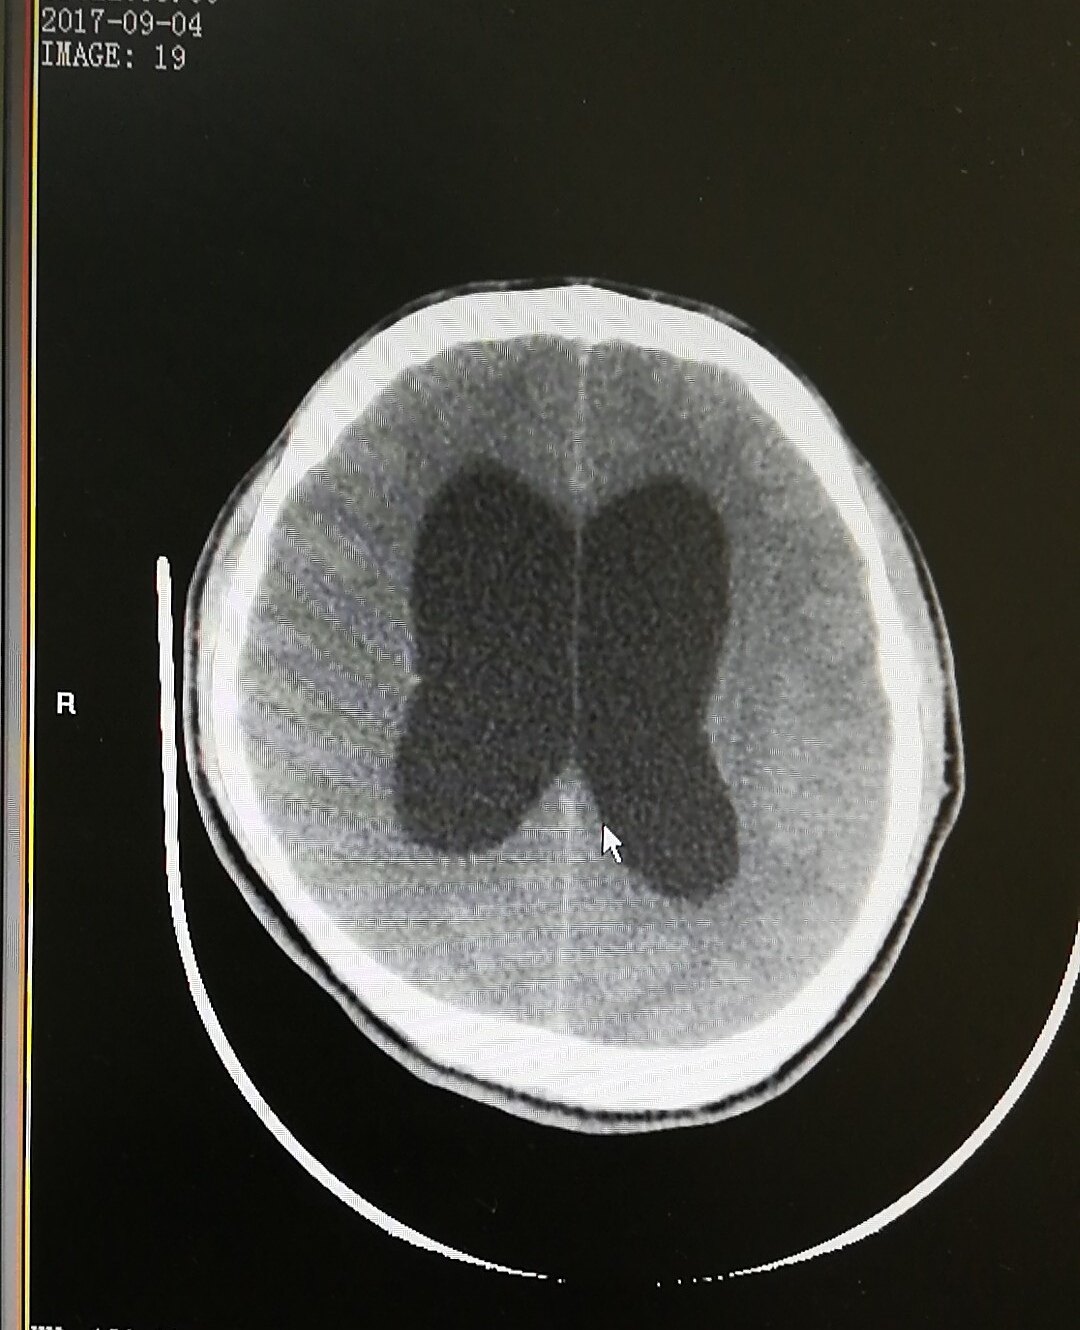

脑血管痉挛(CerebralVasospasm,CVS)是aSAH的常见并发症,通常会导致迟发脑缺血(DelayedCerebralIschemia,DCI),并产生相应临床症状。现在通常认为, 症状性CVS多发生于动脉瘤破裂后的一周内,发生率可达1/3 。

作为神经外科临床常见疾病,aSAH的预后往往不尽如人意, 动脉瘤的二次破裂出血、严重的脑血管痉挛脑干缺血都是病程恶化的重要原因 ,致死率、致残率居高不下。